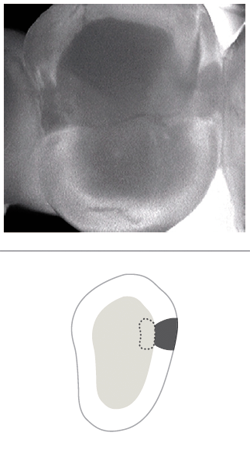

I use CariVu most often to check for interproximal decay that is minimally visible on an X-ray or sometimes not even visible at all. It can help to identify the shape and size of decay in all of its various forms:

• No involvement, sound tooth structure (Fig. 6)

• At the first detectable signs of an enamel caries lesion (Fig. 7)

• An established caries lesion (Fig. 8)

• An established caries lesion that has reached the DEJ at a single point (Fig. 9)

• Dentin caries due to an established enamel caries lesion with extended involvement of the DEJ (Fig. 10)

• Established dentin caries (Fig. 11)